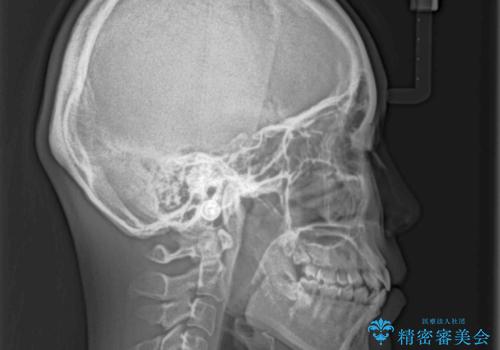

- 口元の突出感と口の閉じにくさ、前歯のデコボコを気にして来院された患者様です。

上下左右第一小臼歯4本を抜歯し、ワイヤー装置にて口元を引っ込めるよう矯正治療を行うこととしました。

骨格的に下顎骨が前方位にあるため、口元の突出感改善には限界があると思われましたが、唇の閉じにくさが改善するほど引っ込めることができました。